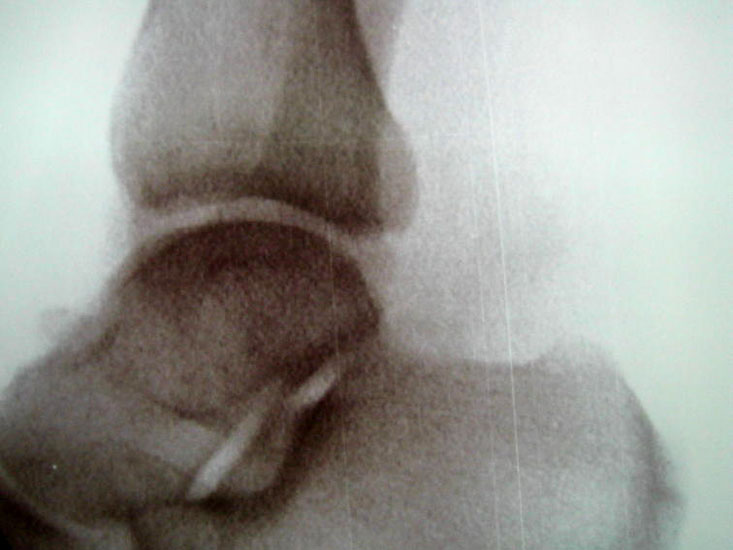

Abbildung Nr. 14-16

Reseziertes Os trigonum sowie prä- und postoperatives seitliches Röntgenbild nach arthroskopischer Entfernung eines Os trigonum.